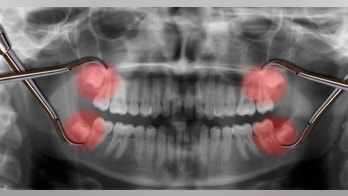

Dental Health - Page 15